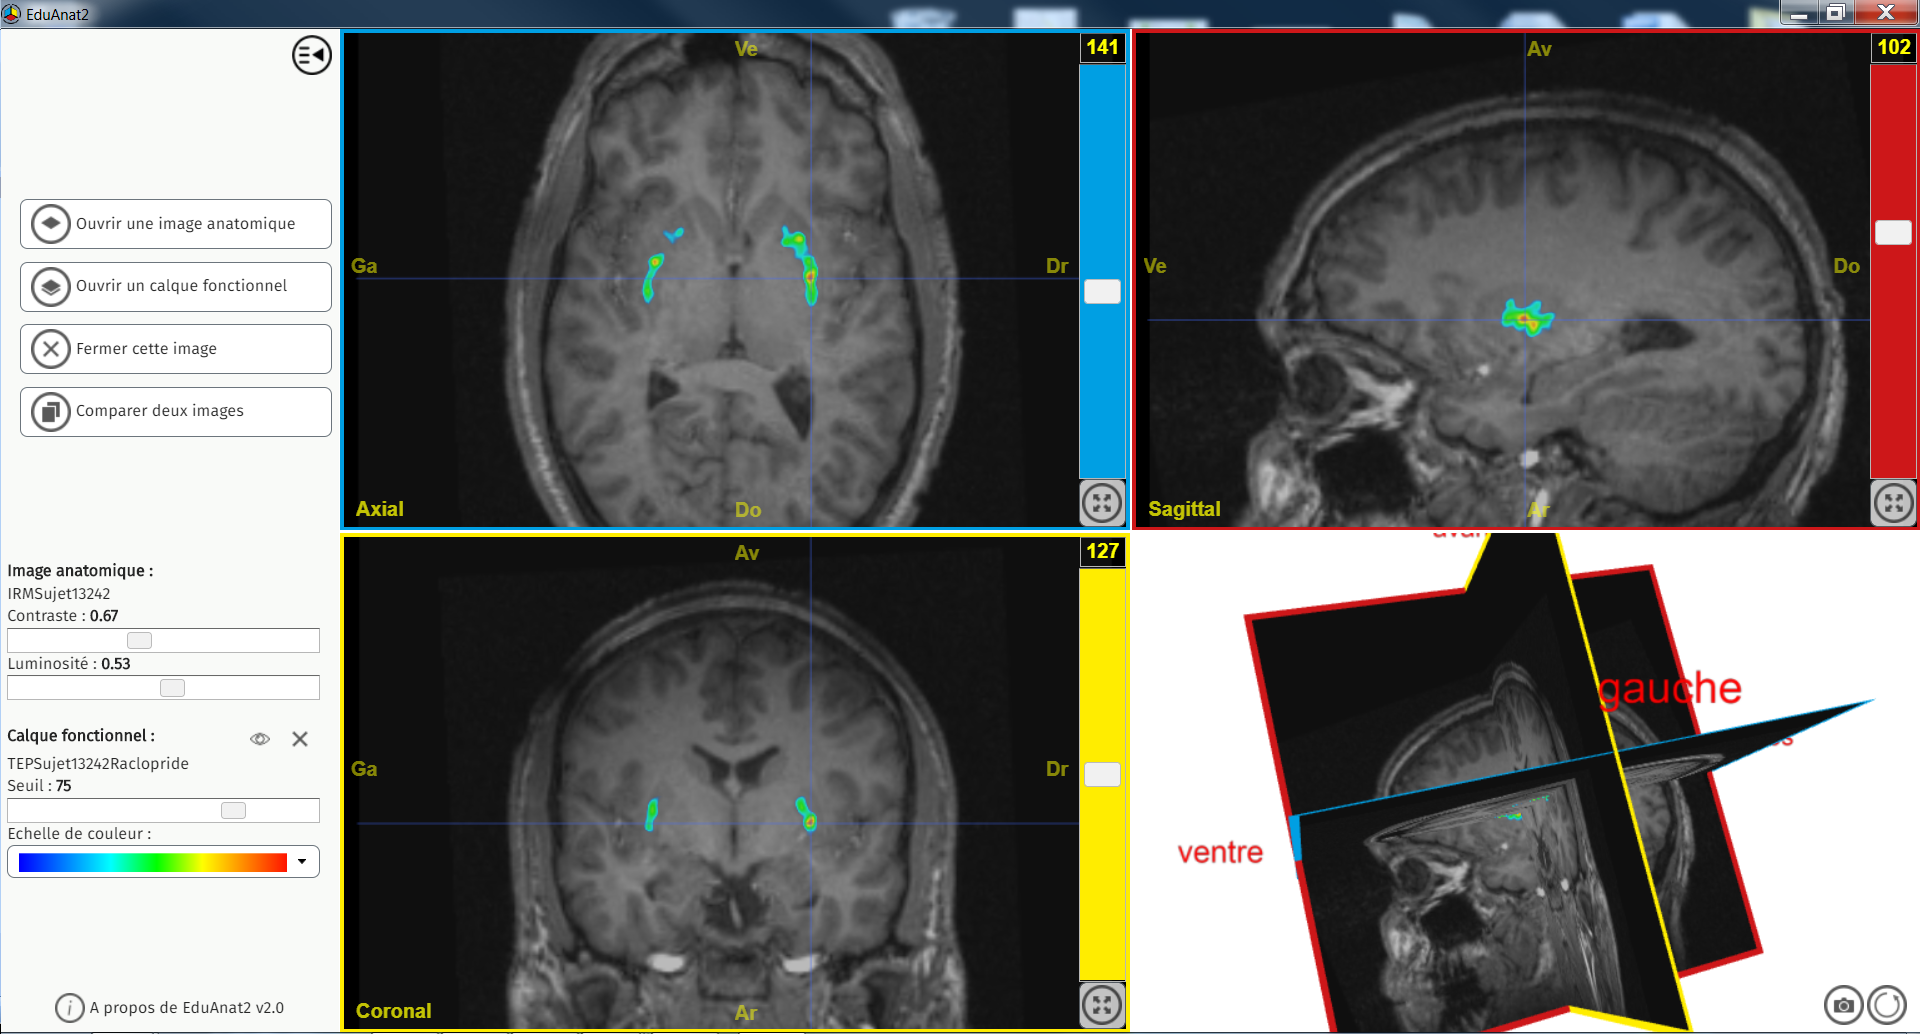

Recepteur D2 Dopamine

Image dans sa taille originale :

1.09 Mo